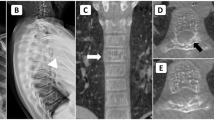

A 39-year-old male was referred to our hospital for endovascular treatment of a right T9 hemivertebral hemangioma with compromise of the spinal canal. Fifteen minutes after the procedure, the patient developed right lower limb weakness and numbness on the left leg. The emergency magnetic resonance imaging (MRI) of the spine showed no abnormalities. Five days later, a new spinal MRI revealed an infarction in the right half of the spinal cord at T6 and T7 level. This stroke was probably caused by a microcoil ended up in the right sulcocommisural artery. One week after surgery, the patient was able to raise the right leg against gravity, but sensory deficit showed no improvement.